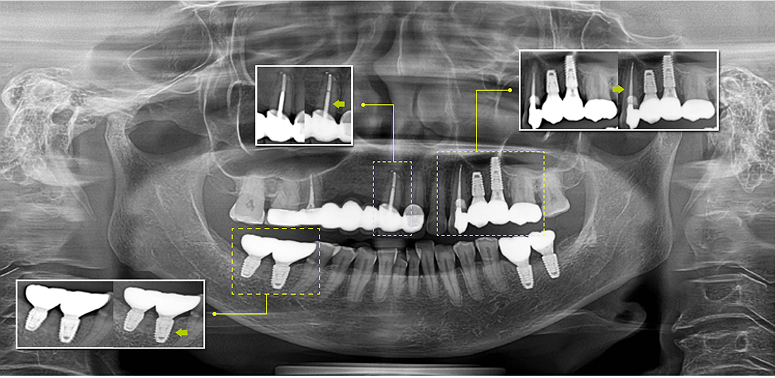

With multi-layered technology, multiple images are taken, and each of those images are further segmented. The system automatically selects the best segments and compiles them into one optimized panoramic image.